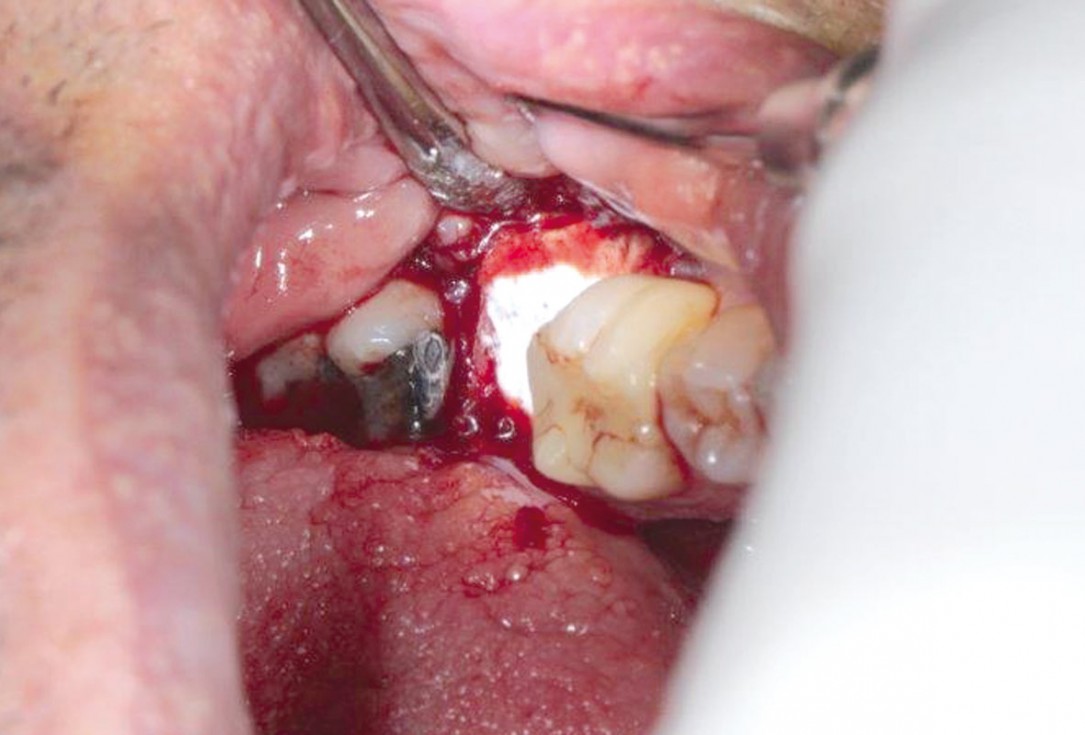

botiss cerabone® & collagen fleece for immediate implantation - Clinical case by Dr. D. Jelušić

Clinical situation before extraction and implantation